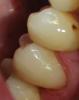

METT Опубликовано 26 апреля, 2013 Автор Поделиться Опубликовано 26 апреля, 2013 24 - пломба выпала,ставили не у нас, на дне плотная неокрашивающаяся пигментация,первое посещение-анестезия-раббердам-подготовка полости под вкладку,на дно SDR-аквапреп-адгезив-слепок,,,второе посещение-анестезия-раббердам-припасовка и фиксация вкладки на композит-полировка,покраска Ссылка на комментарий